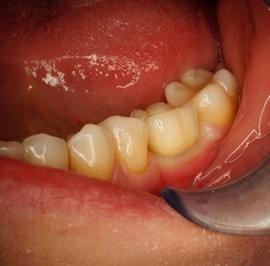

Przedtrzonowce często należą do okolicy estetycznej należy więc zwrócić wzmożona uwagę na poprawną anatomię tkanek kości i dziąsła. Po utracie zęba 25 pacjentka kilka lat chodziła bez jego uzupełnienia, doszło do przesunięcia się zęba 26. U tej pacjentki przed laty był wykonany most jednobrzeżny na czwórce, dość szybko doszło jednak do przeciążenia zęba filarowego, zaniku kości wyrostka i wreszcie pęknięcia korzenia zęba filarowego mostu. Po ekstrakcji i wygojeniu kości stwierdzono ubytek kości wyrostka przekraczający objętość 50% stanu początkowego. Stąd główny nacisk położono na odbudowę tkanek. Uzyskano zadowalający wynik anatomiczny.

Przypadek odbudowy zębów trzonowych z początkowymi znacznymi zanikami kości. Odbudowa kości pionowa i pozioma, następnie implantacja i faza protetyczna.

Podstawą do uzyskania korzystnych wyników leczenia są diagnostyka, określenie planu leczenia i staranne wykonanie wszystkich etapów leczenia. Tutaj przykład pacjentki, u której nie dopilnowano poprawnych stosunków pionowych, przy implantacji. Konieczne było leczenie korekcyjne.

Pacjentka lat 41, odbudowa protetyczna zębów 24, 25 na implantach - korony porcelanowe na metalu. Po stronie prawej zdjęto most 13 - 16, poprawiono warunki kostne wyrostka zębodołowego i wykonano most na implantach od czwórki do szóstki, oraz nacementowano pojedynczą koronę na kła.

Pacjentka lat 50. Most od zęba 24 do zęba 27. Pękł korzeń zęba filarowego 24. Po ekstrakcji wykonano zabieg odbudowy kości wyrostka zębodołowego i podniesiono zatokę. Następnie po skorygowaniu kształtu i objętości dziąsła przytwierdzonego wykonano pojedyńcze korony na implantach 24, 26, oraz most 13-17